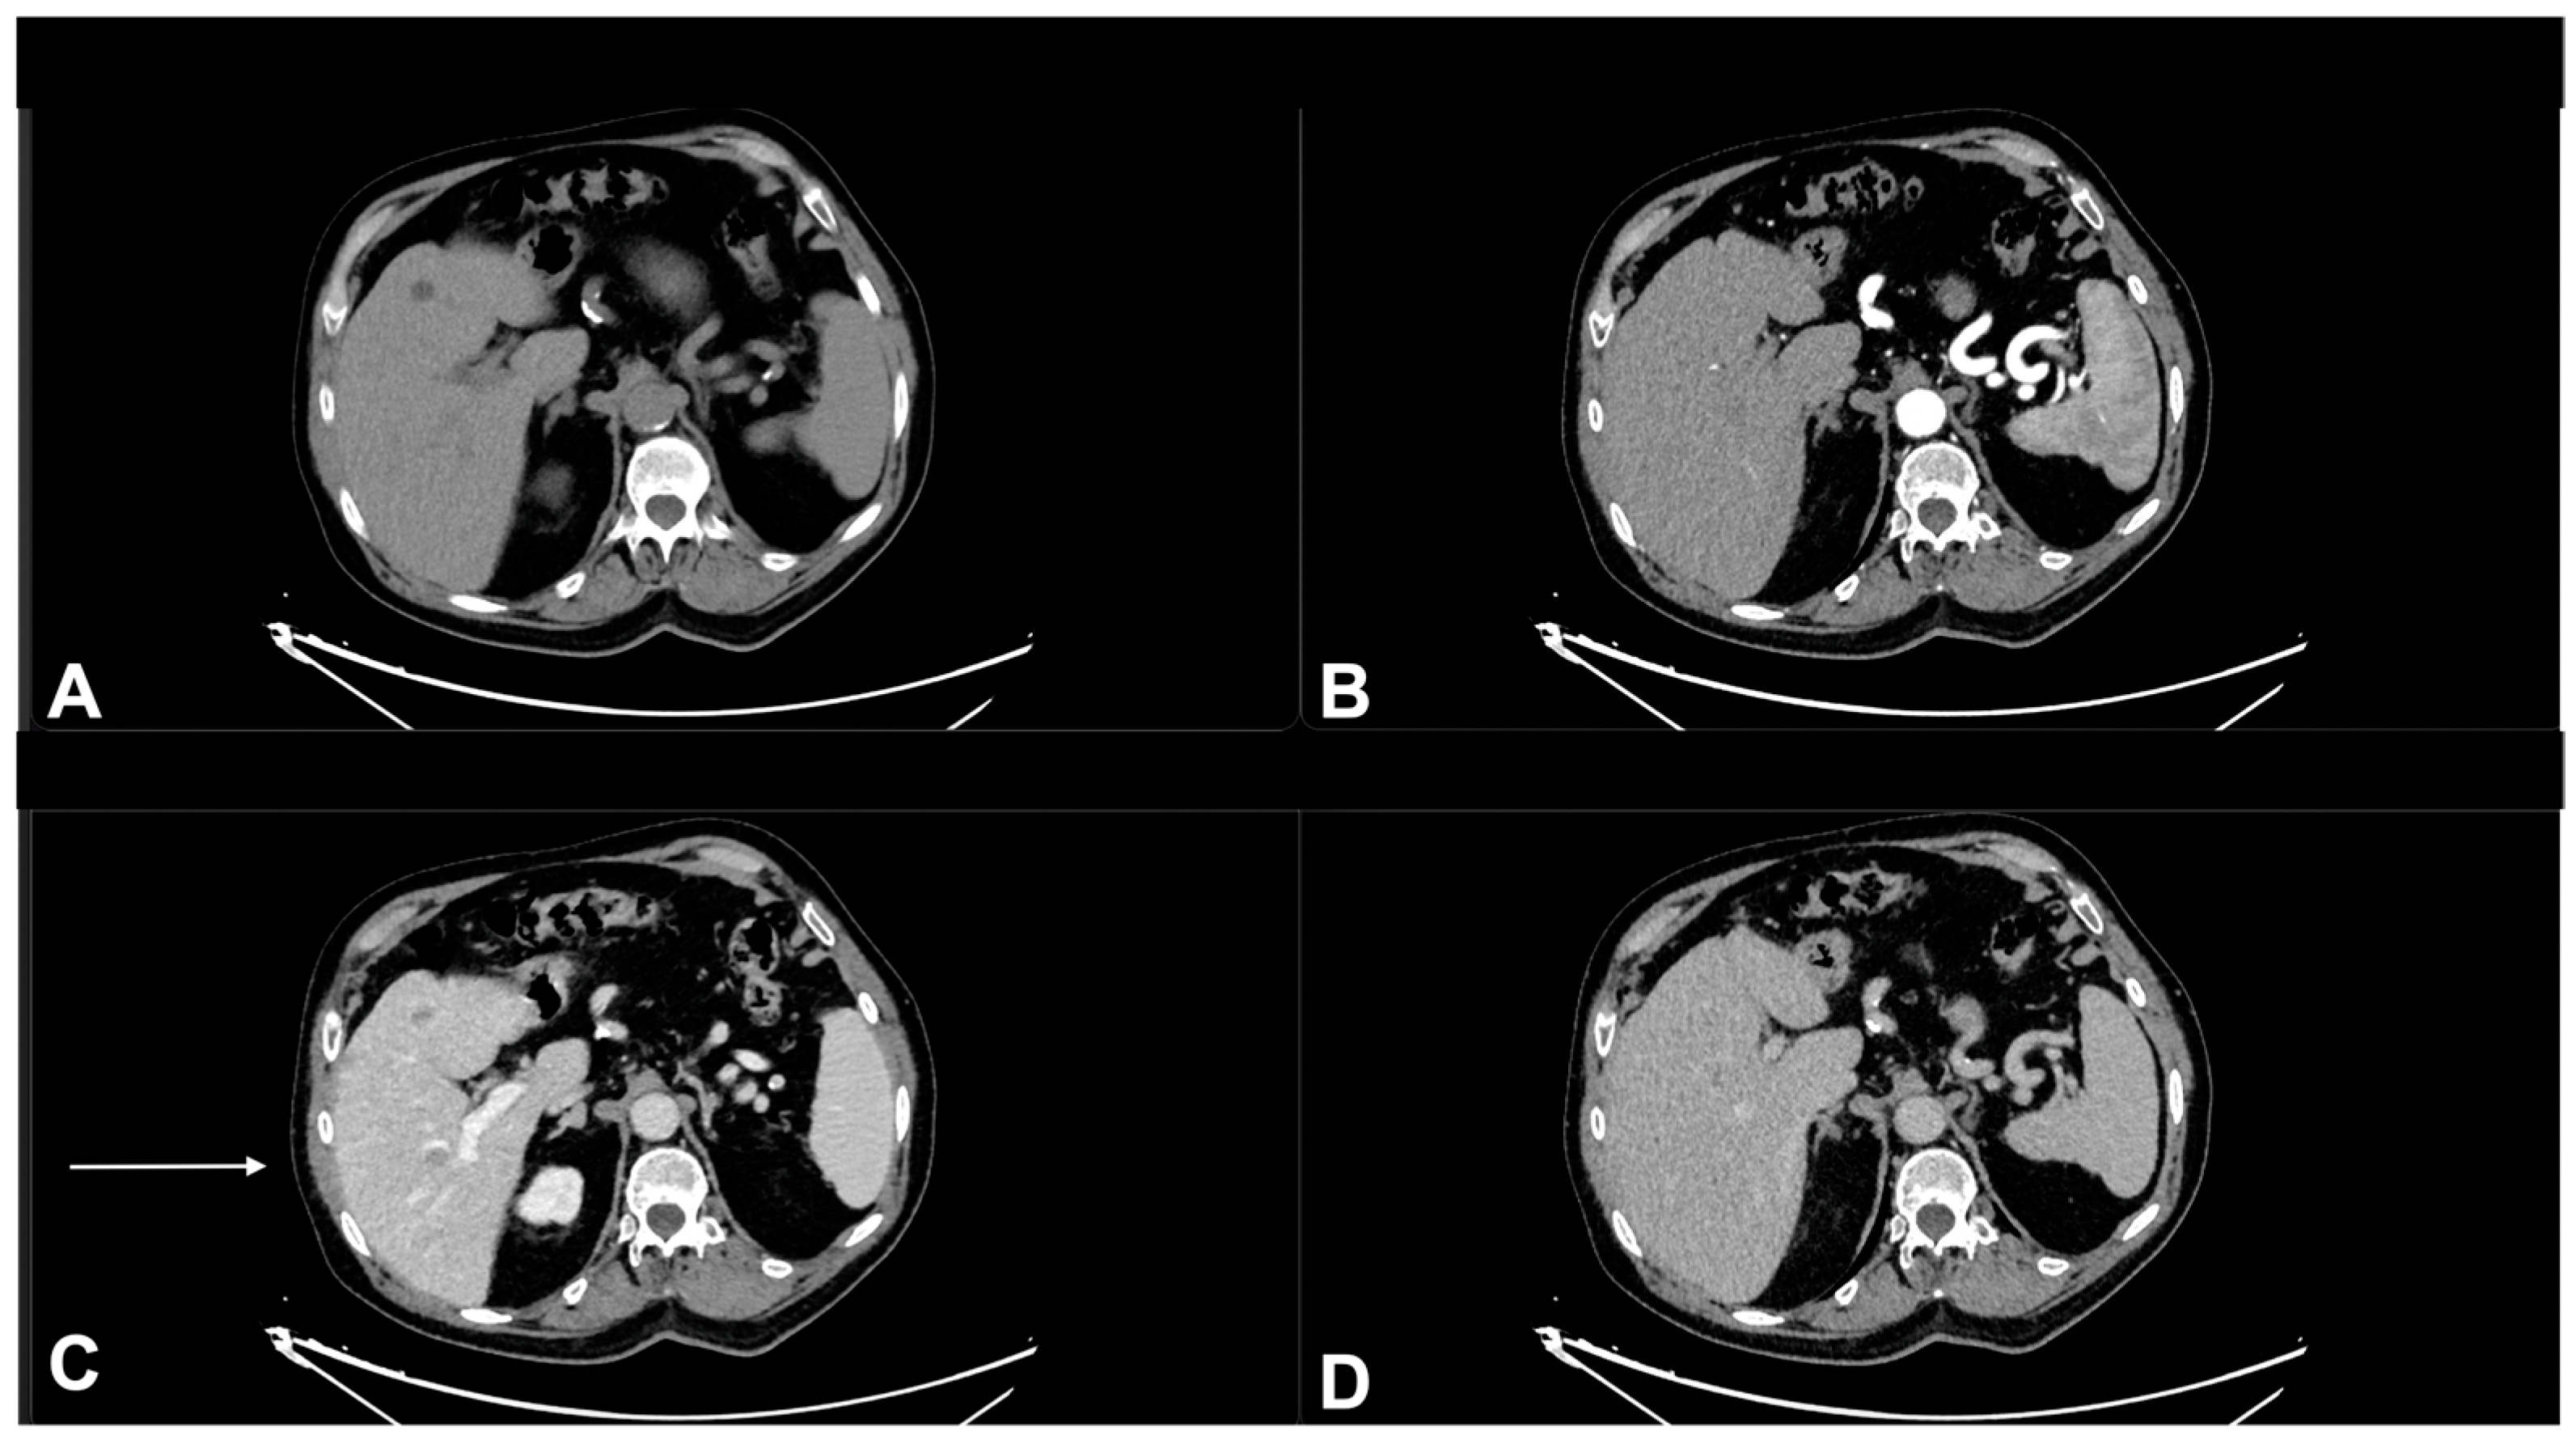

2. Diagnostic Imaging and Non-Melanoma Skin Cancer

3. Diagnostic Tools and Non-Melanoma: Staging and Surveillance